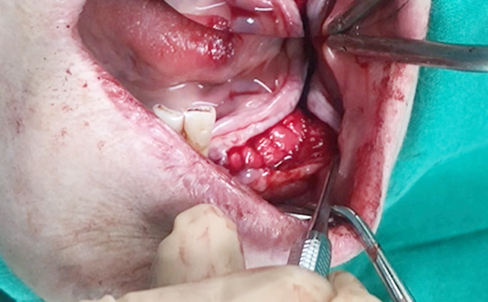

Simultaenous bone grafting for implants

Simultaneous bone graft and implant placement